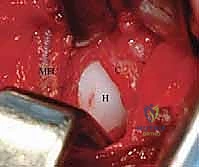

الخطوة 6: تنظيف التجويف الحقي (Clearing the Acetabulum)

الآن، يرى الجراح داخل المفصل. هنا تبرز الخبرة في إزالة العوائق الداخلية:

* يتم استئصال الرباط المدور (Ligamentum Teres) المتضخم الذي يشغل حيزاً كبيراً.

* يتم إزالة الأنسجة الليفية والدهنية المعروفة باسم البولفينار (Pulvinar).

* يتم شق الرباط الحقي المستعرض (Transverse Acetabular Ligament) إذا كان ضيقاً ويمنع دخول رأس الفخذ.

الخطوة 7: الرد الفعلي للمفصل (Reduction)

بعد تنظيف التجويف تماماً، يقوم الدكتور هطيف بتوجيه رأس عظم الفخذ بلطف شديد ليدخل ويستقر بعمق داخل التجويف الحقي. يجب أن يكون الرد مستقراً وسلساً دون الحاجة إلى قوة مفرطة. يتم فحص استقرار المفصل في وضعيات مختلفة للتأكد من عدم خروجه مرة أخرى.